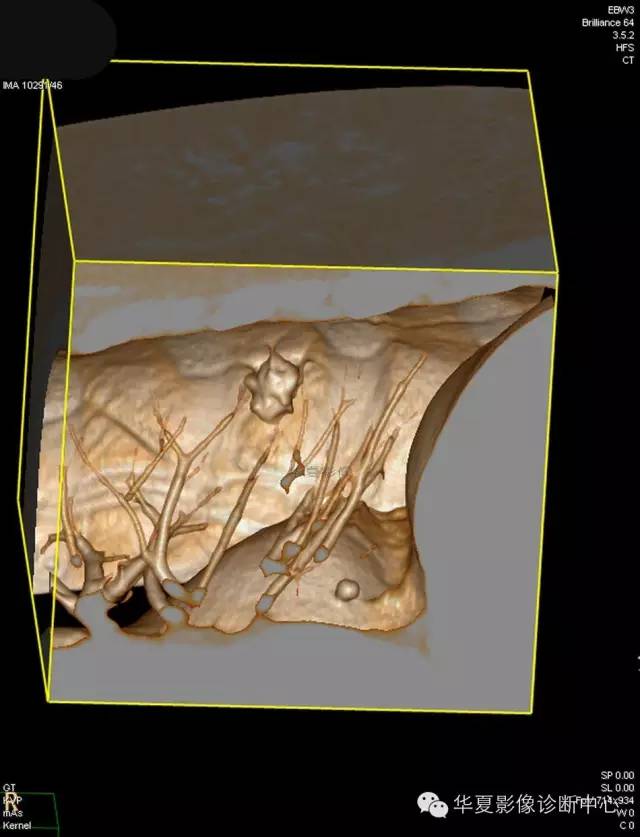

【病例学习】典型周围型肺癌CT病例一例

女,56岁,其父因肺癌去世,自觉胸部疼痛不适来诊要求拍胸片。

1.右肺上叶:肺组织1块,大小13×4×7cm。切面棕红色。2.右肺上叶肿物:灰白色组织一块,大小3×1×1.5cm。切面灰白色。3.右肺中叶结节:灰白色绿豆大组织1块。4.淋巴结:灰黑色绿豆大组织1块。

(右)肺中分化鳞状细胞癌。浸及胸膜。支气管残端切净。淋巴结未见癌转移(0/10)。